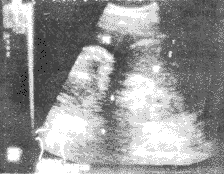

類肺炎性胸腔積液其他輔助檢查:肺的物理檢查結合胸部的X線徵象對中等量以上的積液確定較易,而少量胸腔積液則要通過細緻的檢查才能確定。前後位或側位胸片肋膈角模糊或變鈍,或膈肌模糊者提示有胸腔積液,可改變體位透視或側臥位胸片確定,此時液體散開,肋膈角或膈肌變清晰。CT對胸腔積液診斷效率更高,還可鑑別肺和胸膜病變,了解肺實質病變的位置和特徵,有助於鑑別診斷和指導治療。此外,超音波檢查也可確定有無胸腔積液存在和穿刺定位。